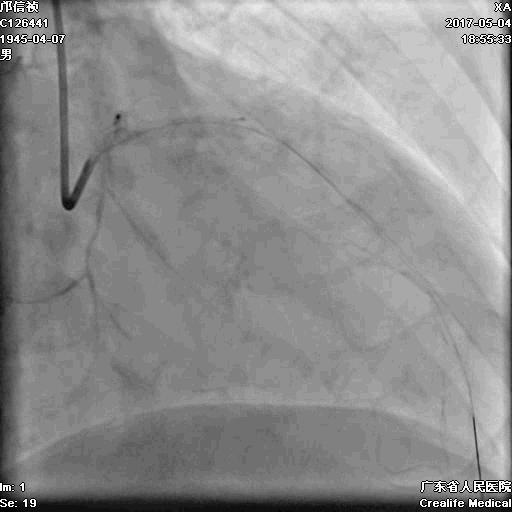

RRA:6F AL0.75 GC –RCA;

RFA:7F XB 3.5 GC—LCA 150cmcorsair

正向130cmFinecross微导管支持下尝试送PILOT150、Gaia 2导丝无法通过RCA闭塞段

SION导丝通过侧枝

逆向导丝:更换Gaia2

正向导丝:Gaia2,PILT150

正向导丝knuckle

2.5*15mm球囊扩张,逆向导丝尝试,但未能进入正向GC

1.正向2.5*15mm球囊扩张,Reverse CART

2.Guidezilla延长导管辅助下,逆向导丝进入正向GC